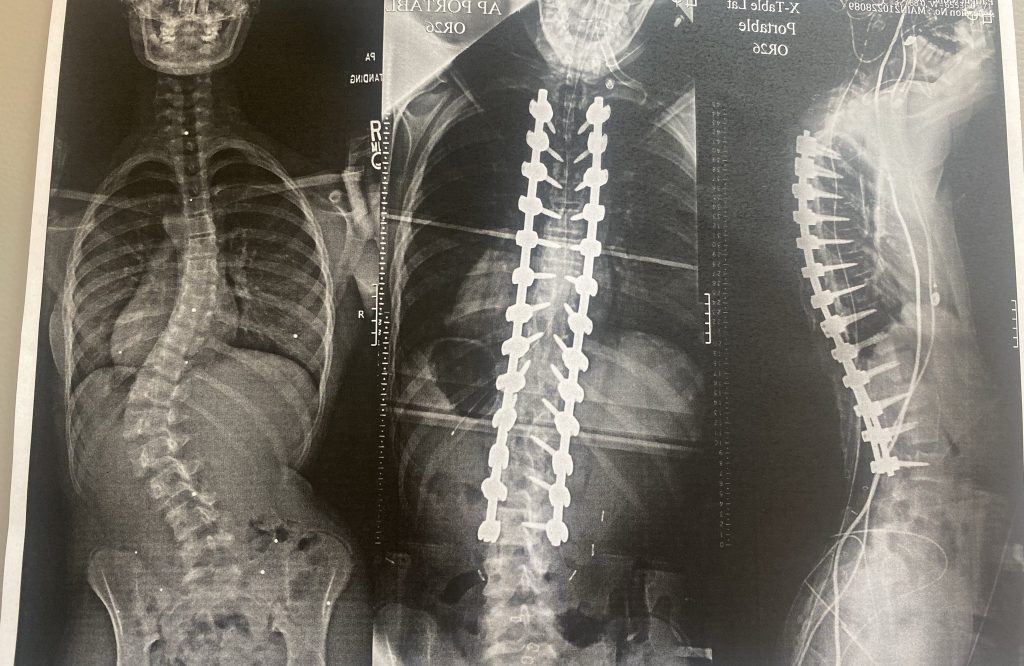

I was 13 years old when we discovered that I had scoliosis. I never really had any back pain but all of a sudden we started noticing a curve in my spine. When we visited Dr. Widmann, my x-ray showed that my curve was over 60 degrees. Surgery was my only option. Dr. Widmann suggested to get a another opinion which we did, but in the end we decided to have Dr. Widmann perform the spinal fusion.

I had my spine fused from L3 to T3. At that time I was very nervous because I play soccer and I was scared that this would stop me or holding me back from playing again. But I totally trusted Dr. Widmann and him and everyone made me feel safe and comfortable.